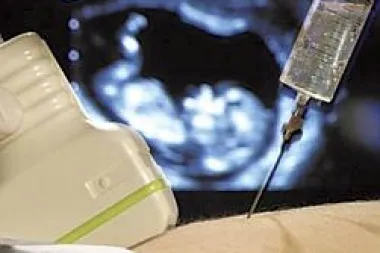

Svaka buduća majka želi od prvog dana svoje trudnoće je li njezino dijete zdravo i hoće li takvo ostati. Moderna tehnologija, 3D i 4D ultrazvuci, te različite druge pretrage već vrlo rano mogu otkriti je li s plodom sve u redu, te postoje li kakvi poremećaji. Ipak, jedan od najpouzdanijih pretraga, što se tiče utvrđivanja zdravlja ploda, u ranim fazama trudnoće je amniocenteza, za koju se ne odlučuje veliki broj žena, jer se smatra da ukoliko ultrazvučne pretrage ne pokažu abnormalnosti ploda, te u obitelji ne postoje određene indikacije da bi se taj postupak trebao obaviti, ona se izbjegava. Što je ustvari amniocenteza? Radi se o testiranju plodne vode, koja se nalazi okolo ploda u razvoju. Postupak se provodi na način da se kroz abdomen i maternicu uvede igla, u područje oko ploda, ali na način da se ne dira niti plod niti posteljica. Uzima se vrlo mala količina plodne vode, po prilici 14. grama, odnosno količina od jedne do dvije jušne žlice. Nakon toga, plodna voda ide na genetsku analizu, jer se u njoj nalaze stanice od ploda, pa se tako mogu dobiti iz nje sve potrebne informacije o zdravlju ploda. Amniocenteza se najčešće radi između 15. i 18. tjedna trudnoće, no može se napraviti i prije 14. tjedna iako to baš nije praksa, jer je plodne vode tada još vrlo malo, pa postupak može izazvati pobačaj, a šanse za to su 1 naprema 200. Nakon 32. tjedna amniocentezom se može provjeravati razvijenost pluća od djeteta.   Kome se preporuča amniocenteza? Kao što smo naglasili, amniocenteza nije uobičajen postupak koji se obavlja ili preporučuje svim budućim mamama, nego za to njega najčešće moraju postojati određene indikacije. Tako se ona preporučuje trudnicama koje imaju više od 37 godina, ženama koje su već rodile djecu s Downovim sindomom, zatim Bifida Spina (rascjepom kralježnice), anencefalijom ili encefalokelom. Također, ova pretraga preporuča se onima ženama koje znaju da u obitelji postoje određene rijetke genetske abnormalnosti. Ukoliko se pitate zbog čega se trudnicama iznad 37 godine života preporuča amniocenteza, razlog su njihove godine zbog kojih u trudnoći postoji veći rizik za genetskim abnormalnostima, a jedan od najčešćih je Downov sindrom.  Naime, kod starijih trudnica šanse da rode dijete s Downovim sindromom znatno se povećavaju i iznose 1 naprema 100. U trudnoći nakon 40. godine života šanse su još veće.

Kako se pripremiti na amniocentezu? Detalje postupka saznat ćete od liječnika, no evo određenih smjernica koje možete očekivati i koji se poželjno držati. Najbolje je da na amniocentezu dođete s punim mjehurom, jer pun mjehur podigne maternicu s bebom, što olakšava pregled na ultrazvuku. Slijedi detaljan pregled na ultrazvuku, gdje se utvrđuje položaj posteljice, te se isključuje eventualna trudnoća s blizancima. Nakon pregleda ultrazvukom, područje trbuha se detaljno čisti, te započinje postupak s iglom, koja se polako uvodi područje trbušne šupljine i maternice. Položaj igle cijelo vrijeme se nadzire ultrazvukom. Postupak traje vrlo kratko, jer je potrebno oko minute da se izvuče potrebna tekućina. Nakon toga, igla se vadi, slijedi ponovni pregled ultrazvukom, a ako je sve u redu, majka može kući. Preporučuje se mirovanje do kraja dana, a nakon toga, buduća majka može obavljati sve uobičajene aktivnosti. Postoji mogućnost manje neugodnosti nakon postupka, no ne bi smjelo biti jačih bolova, gubitka krvi ili istjecanja plodne vode. U protivnom, potražite hitnu pomoć.